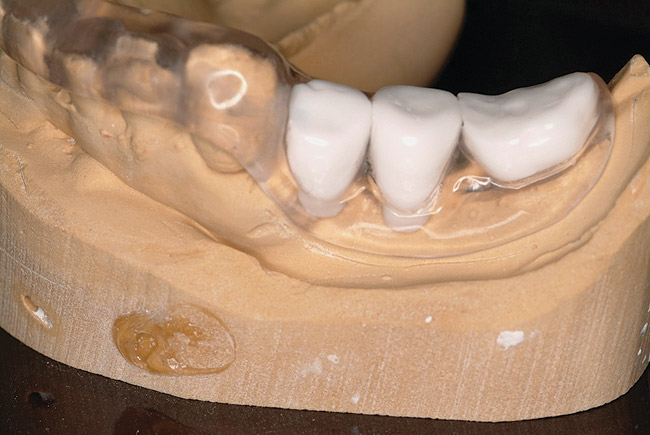

In esthetically sensitive areas of the dentition, precise implant positioning can be the most critical factor in achieving acceptable results for patients. No area can be more amenable to the accuracy of guided placement. Planning software is capable of measuring the distances of implants from adjacent teeth, as well as inter-implant distances (Figure 20). Whether the prosthetic connection of the proposed implants are of a "platform-shifted" or "butt-joint" nature, these distances, which can determine whether esthetic treatment outcomes are acceptable or not, can be pre-determined by combined evaluation of diagnostic wax-up, virtual implant and prosthetic design, and placement within various software packages prior to executing any type of surgical procedures. When 3-dimensional positioning of the implants is pre-planned and both the oral surgeon and restorative dentist are satisfied that anatomic and esthetic principles have been optimized "virtually," a surgical guide can be fabricated to predictably place the planned implants into these pre-determined positions. This will take much of the guesswork out of traditional implant therapy, and give patients and clinicians greater confidence in the outcome of treatment.

Figure 20  Inter-implant and tooth‚Äìimplant distances predetermined with planning software.

Figure 20